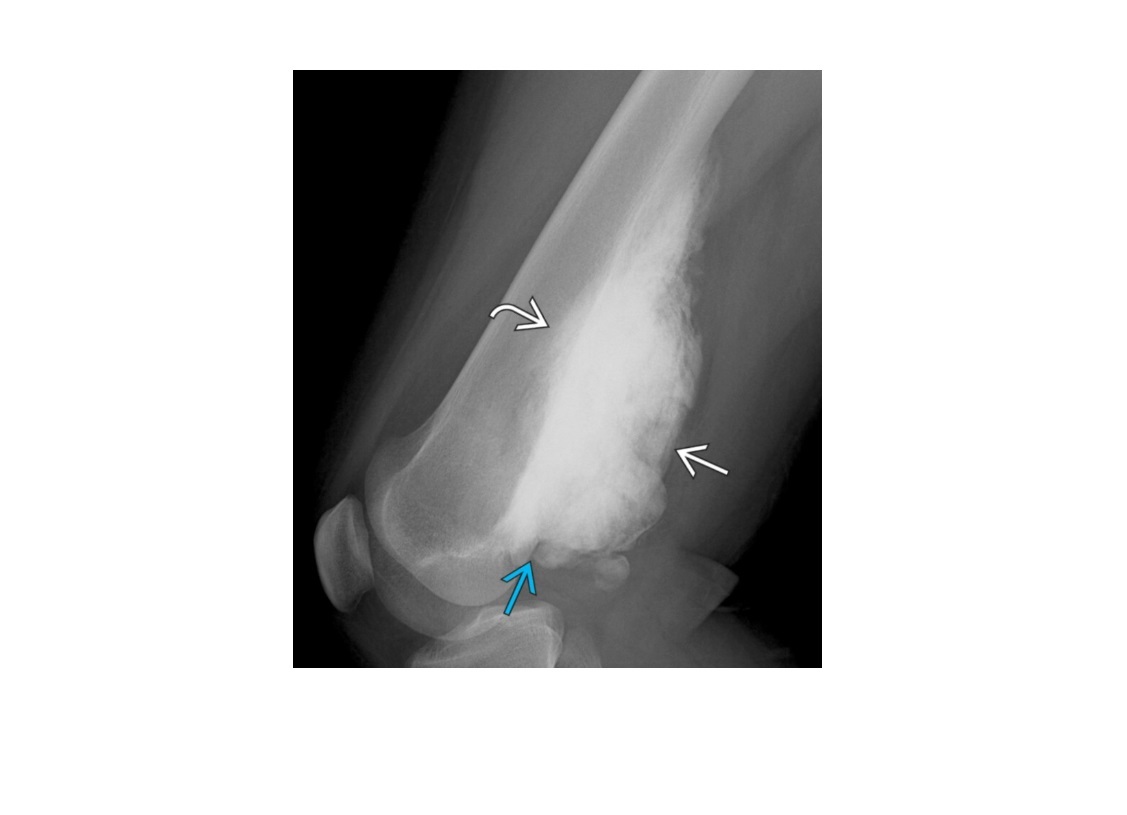

osteosarcoma

Femur (40%) and proximal tibia commonest sites (15%)

**Aggressive periosteal reaction **

- Sunburst

- Codman triangle

- Lamellated (onion skin)

**High grade = Met to the lung

**

Reverse zoning phenomenon - dense mature matrix in the centre, less peripherally

DDx

ewings Sarcoma